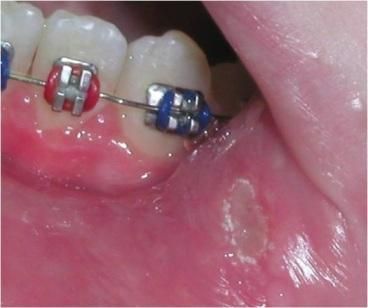

- Afta-Herpes

Applicazioni Cliniche